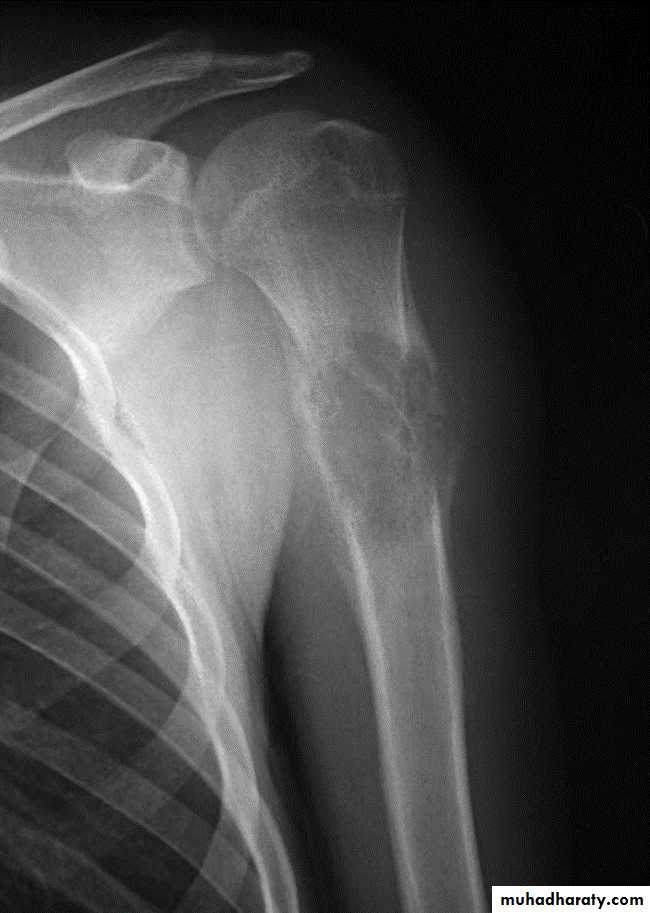

Area of bone destruction or sclerosis with ill-defined margins, wide zone of transition & periosteal reaction with or without cortical destruction & soft tissue swelling.Osteosarcoma :

Age: 5-20-yrs, elderly with Paget's disease.Site: metaphyseal around the knee joint.

Findings:

Lytic

Blastic

Mixed

Poorly defined bony destruction.

Sun ray speculation (periosteal reaction).

Elevation of the periosteum at the margin producing the so called Codman's triangle.

Cortical destruction.

Soft tissue swelling.